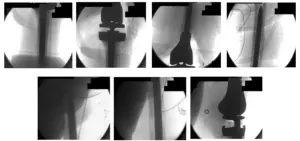

Intraoperative Fluoroscopy Images